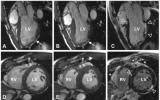

Charité-Universitätsmedizin Berlin համալսարանի եւ Max Delbrück Center կենտրոնի գերմանացի գիտնականներն առաջին անգամ սրտաբանական հետազոտությունների համար 7Տ-ՄՌՏ են օգտագործել: Կարդիովասկուլյար մագնիսառեզոնանսային...